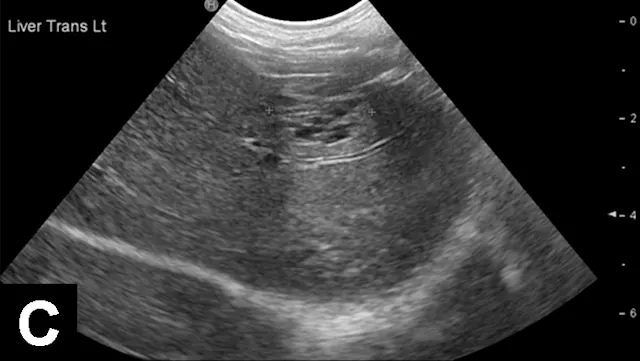

Figure 1A

In each of these cases, histologic diagnosis was made using fine-needle aspirates of the liver (vacuolar hepatopathy, hepatic lipidosis, acute severe neutrophilic hepatitis, respectively). Transverse image (A) of the left side of the liver in a normal dog showing hepatic vein (arrows) and portal vein (arrowheads). Hyperechoic liver (B) secondary to glycogen accumulation resulting from Cushing’s disease in a dog. Note the decrease in portal vascular markings. Hyperechoic and hyperattenuating liver (C) secondary to hepatic lipidosis in a cat. Note the hypoechoic falciform fat in the near field (≤1.5 cm deep) relative to liver echogenicity. In addition, there are some contact artifacts resulting in hyperechoic lines as well as the normal lines of abdominal musculature in the extreme near field (<0.5 cm). In normal cats, falciform fat and hepatic echogenicity are isoechoic to each other. In the far field, hyperattenuation of the ultrasound beam results in image dropout (starting at a depth of 3.5 cm). Hypoechoic liver (D) secondary to acute hepatitis in a dog. Note the marked decrease in echogenicity relative to the spleen.